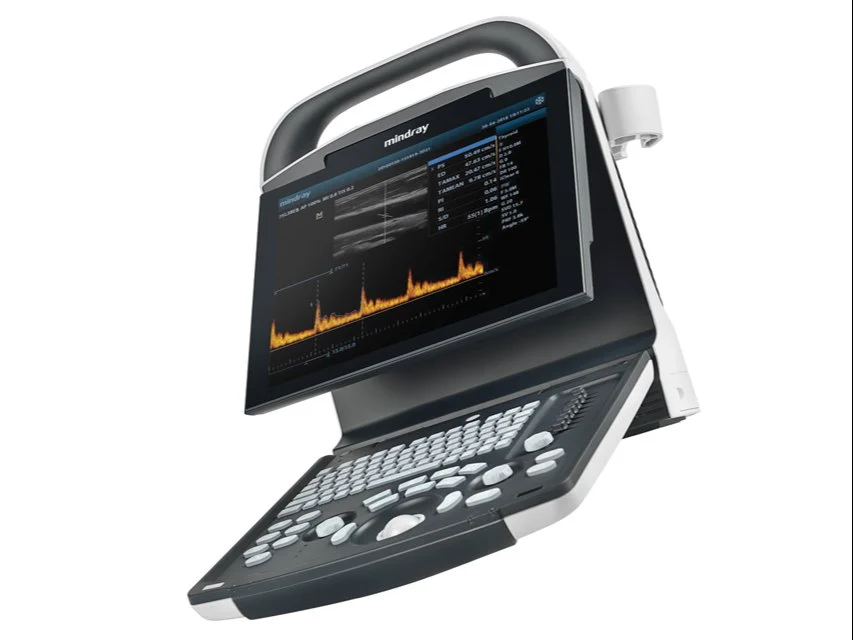

Mindray DP-21 Power Digital Ultrasound Machine

An ideal choice for an entry-level black & white ultrasound system, DP-20 comes equipped with a best-in-class combination of performance and affordability. With a new platform based on Intel’s powerful processor, DP-20 forms an integral part of Mindray’s new generation of portable B/W ultrasound systems equipped with the latest imaging technologies and convenient workflow options.

- 12.1″ high definition LED with full screen design

- Ergonomic Mobile Design with full screen

- Light and compact design for extreme portability

- 30 degree tilting angle adjustable monitor

- One universal transducer connector

- User friendly control panel with backlit